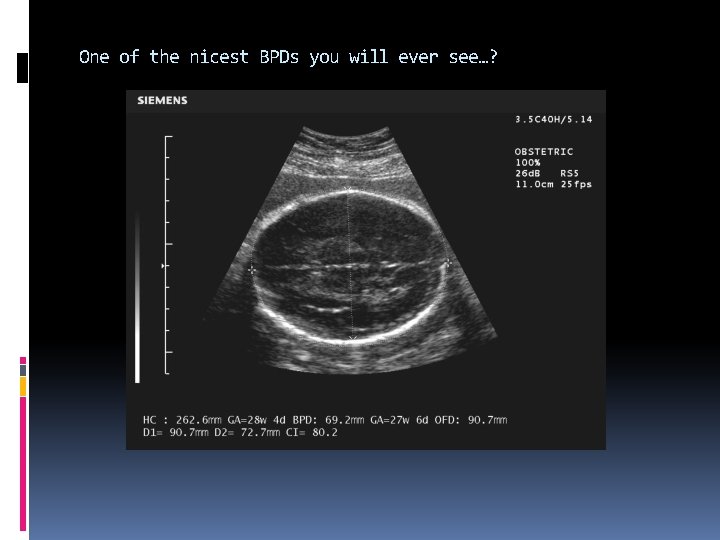

One of the nicest BPDs you will ever see…?

HC Head Circumference Measured at the same level as BPD Circumference should not include scalp echoes when using electronic ellipse software. When occipito-frontal OFD measurements are used in conjunction with BPD, the OFD should be measured Outer edge to outer edge. More accurate than BPD when the fetal head is dolichocephalic or brachycephalic

Head circumference